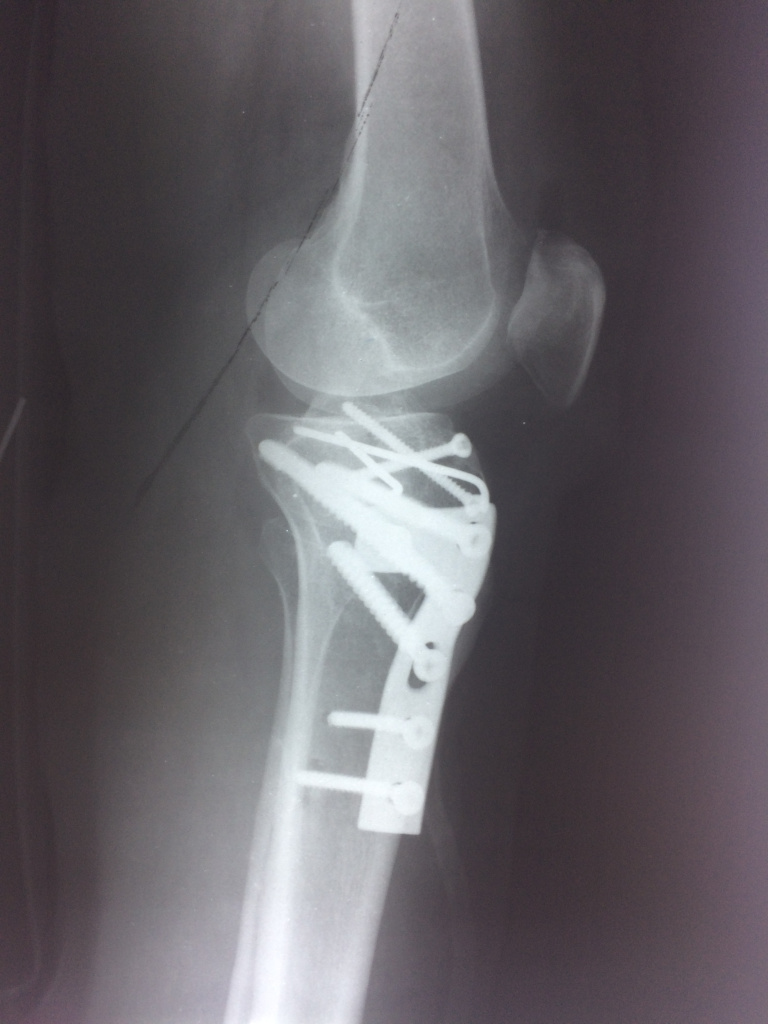

Использование материала Остеоматрикс при импрессионном оскольчатом переломе наружного мыщелка большеберцовой кости по типу Schatzker II

Использование материала Остеоматрикс при импрессионном оскольчатом переломе наружного мыщелка большеберцовой кости по типу Schatzker II.

Операция - открытая репозиция, остеосинтез большеберцовой кости опорной пластиной с костной ксенопластикой маетриалом "Остеоматрикс". На контрольных снимках в три и шесть месяцев имеется консолидация перелома, миграции фиксатора нет, имеется остеоинтеграция ксенопластического материала. Функция коленного сустава полная.